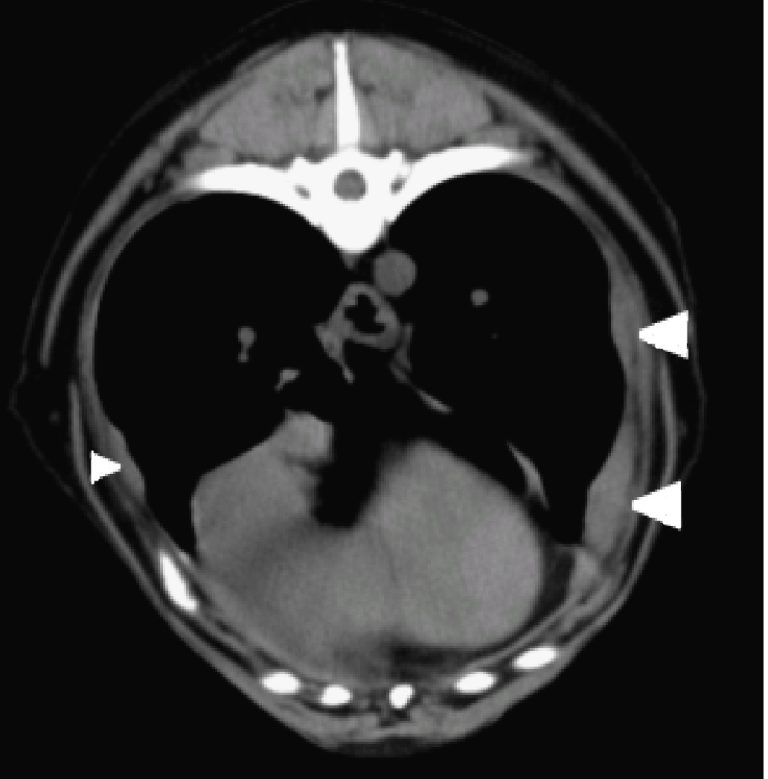

A röntgennél és ultrahangos vizsgálatnál érzékenyebb a mellüregi, hasüregi CT vizsgálat, ami előtt javasolt a folyadékot lecsapolni az altatási kockázat csökkentése és a képalkotás diagnosztikai értékének növelése miatt. CT felvételeken gyakran – de nem minden esetben – látható a savóshártyák lokális megvastagodása, kontraszthalmozása.

Mellkasi CT-n látható mellhártya megvastagodás -nyilakkal jelölve